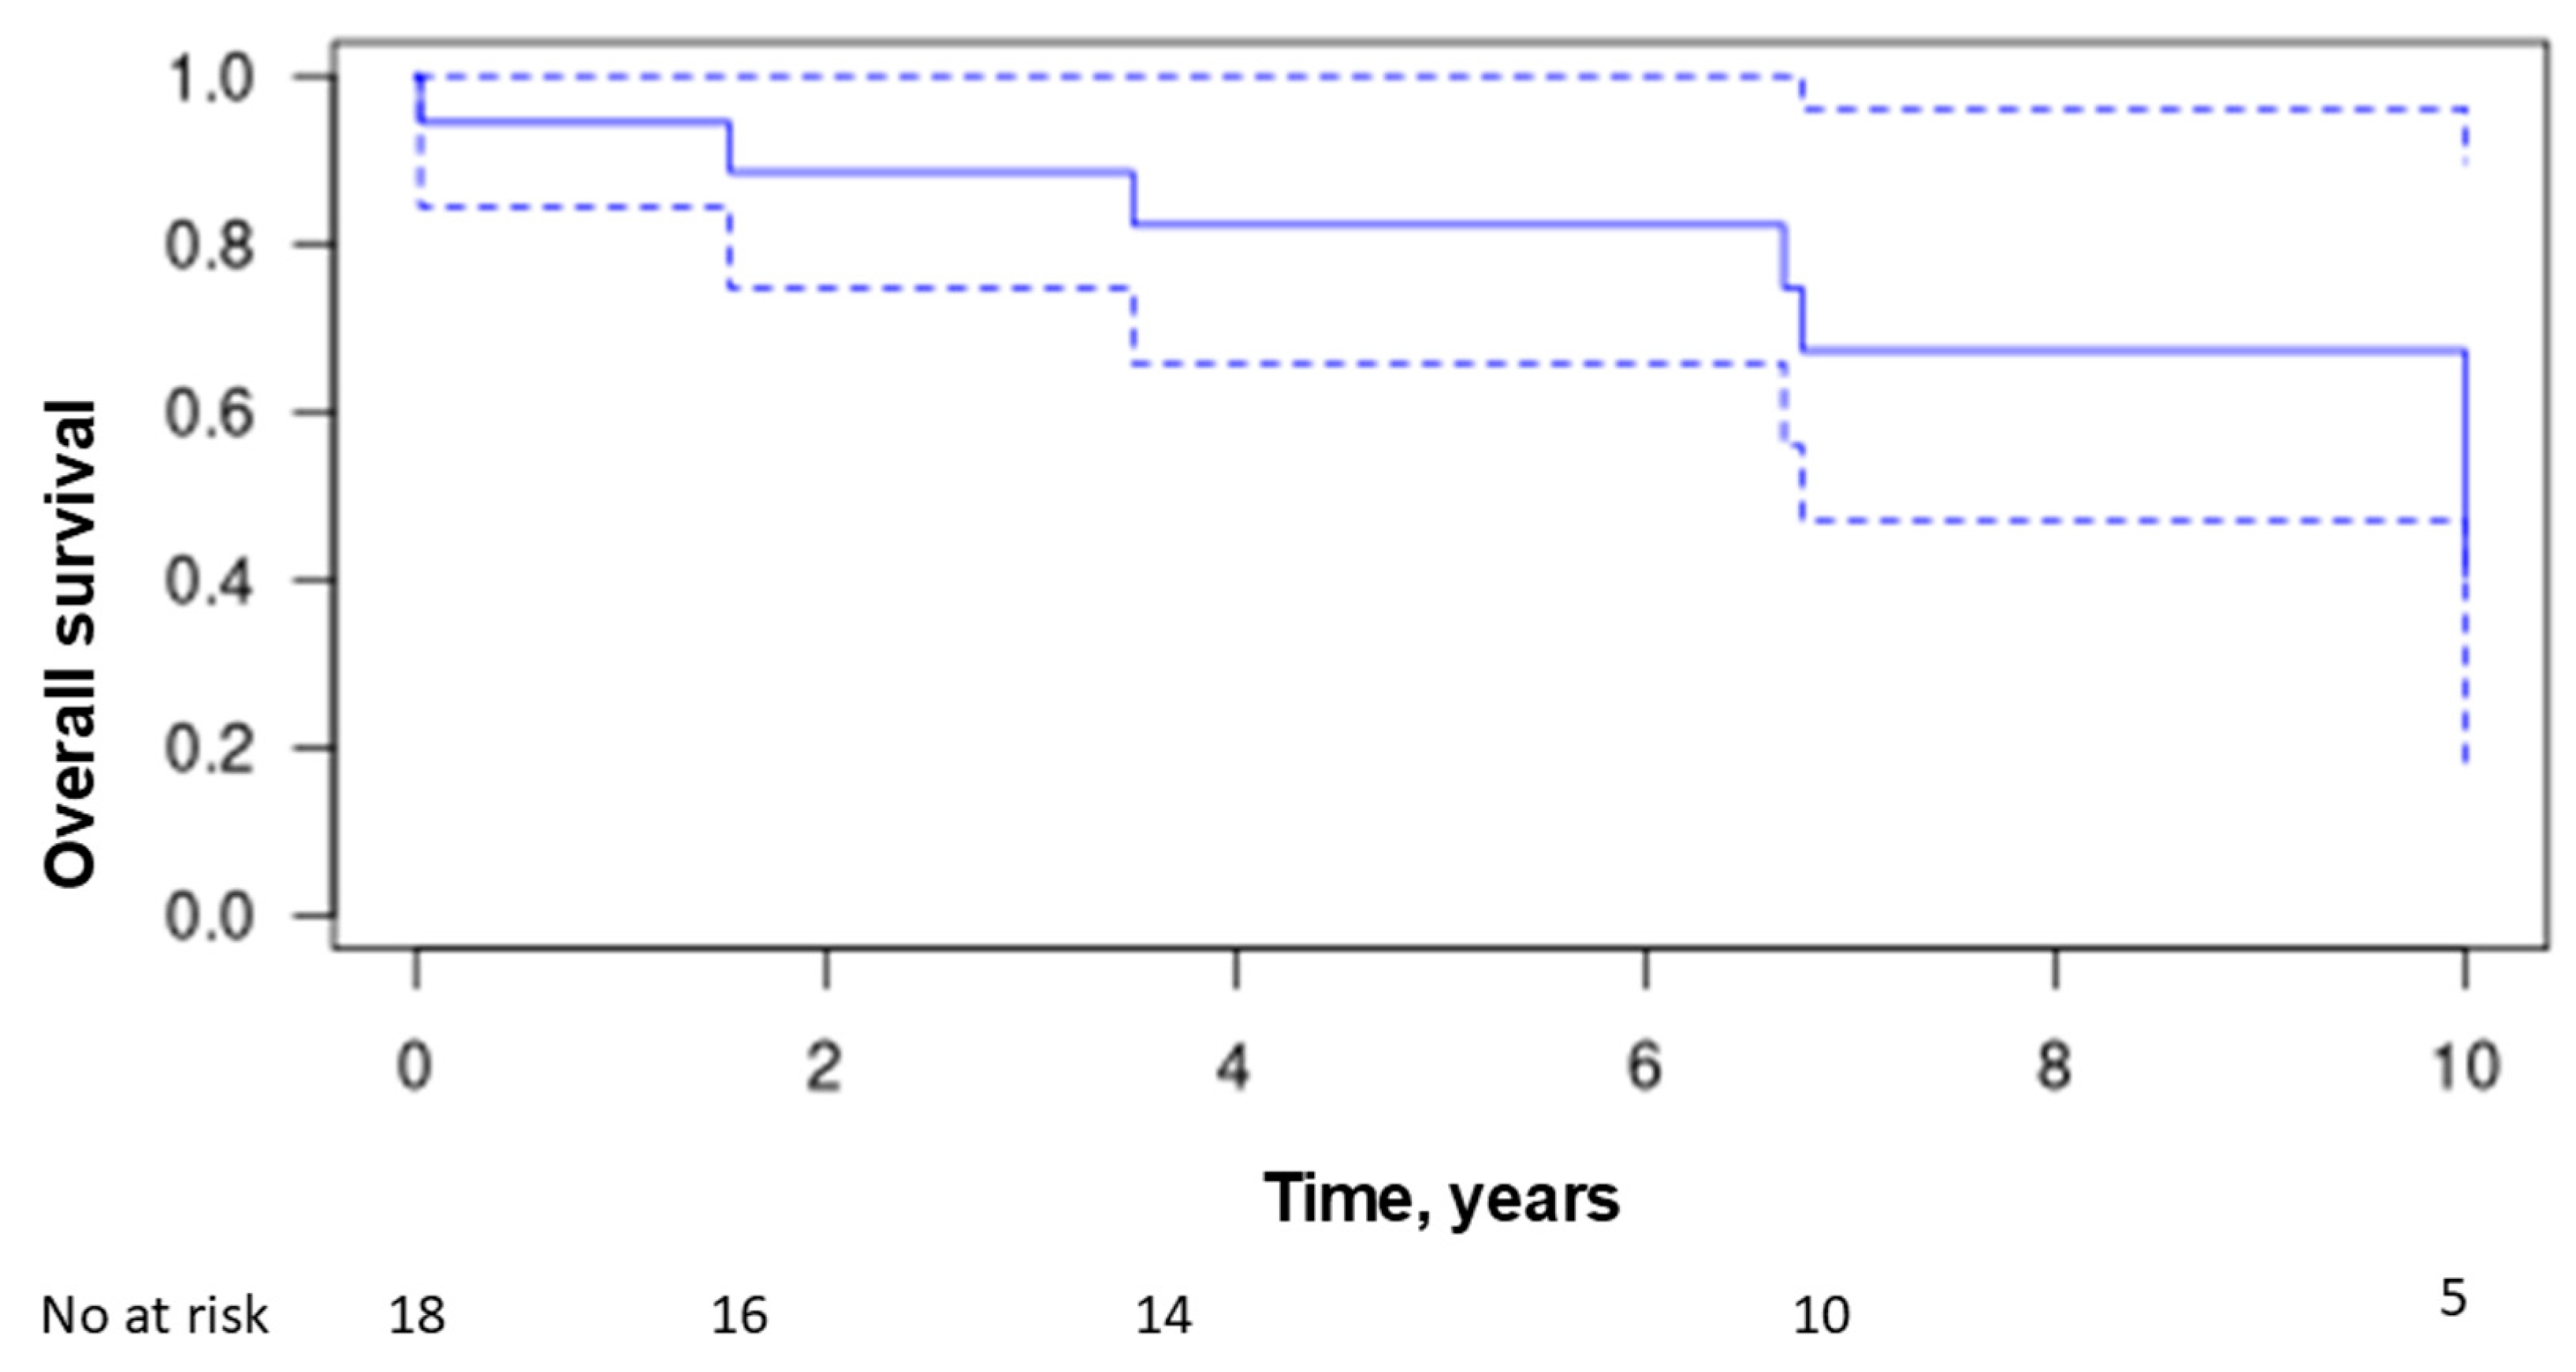

3.8. Treatment and Outcome

4. Discussion

5. Conclusions